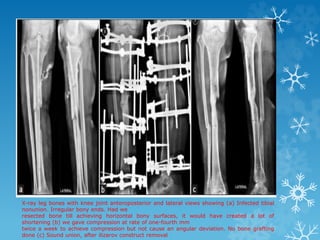

X-ray leg bones with knee joint anteroposterior and lateral views showing (a) Infected tibial

nonunion. Irregular bony ends. Had we

resected bone till achieving horizontal bony surfaces, it would have created a lot of

shortening (b) we gave compression at rate of one-fourth mm

twice a week to achieve compression but not cause an angular deviation. No bone grafting

done (c) Sound union, after ilizarov construct removal

X-ray leg boneswith knee joint anteroposterior and lateral views showing (a) Infected tibial nonunion. Irregular bony ends. Had we resected bone till achieving horizontal bony surfaces, it would have created a lot of shortening (b) we gave compression at rate of one-fourth mm twice a week to achieve compression but not cause an angular deviation. No bone grafting done (c) Sound union, after ilizarov construct removal